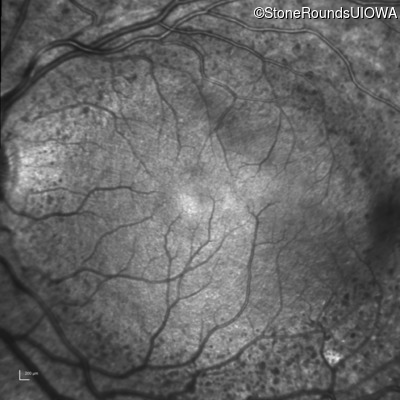

Infrared Fundus Photograph - Right - 20/50

Exemplar